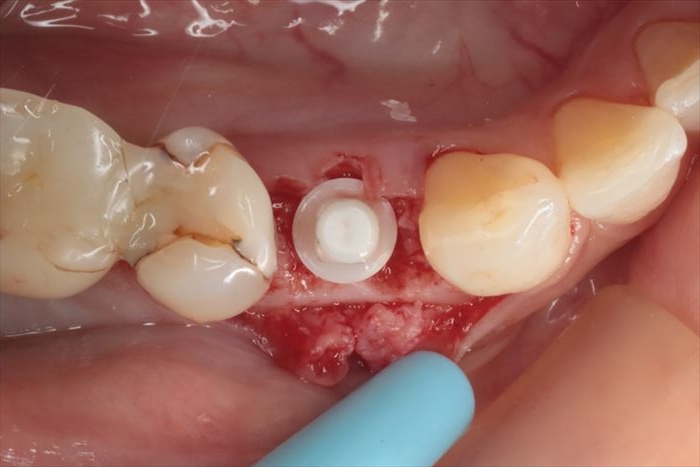

サージカルステントを利用してドリリングし、深度ゲージを挿入しました。

最終ドリルまでドリリングを終えました。

粘膜を剥離して骨の位置を確認します。

骨内にジルコニアインプラントの埋入を終えました。

ジルコニアインプラントは、いわゆるアバットメントまでが一体となったワンピースインプラントですので

適切な埋入位置・埋入深度・埋入トルクが要求されるため、術者にとっては難易度が高い治療と言えます。

最終的にかぶせる歯冠形態を常に意識しながら埋入することが重要です。